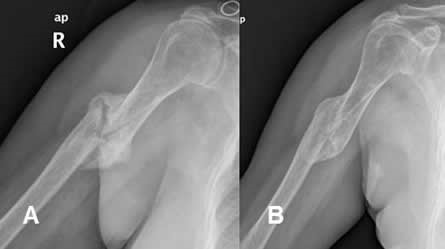

El síndrome de Bertolotti es una anomalía congénita de la región lumbosacra de la columna vertebral que se caracteriza por el desarrollo de una apófisis transversa anormalmente grande, una megaapófisis en la última vértebra lumbar.

Este crecimiento anómalo, aunque está presente desde el nacimiento, no se detecta habitualmente hasta la edad adulta, bien como hallazgo radiológico asintomático en un control de rutina o por la aparición progresiva de dolor lumbar, situación esta última mucho más frecuente.

La presencia de una apófisis transversa anormalmente grande da lugar a una fusión total o parcial al sacro y una perturbación en la proximidad de la cresta iliaca con la que puede rozar, colisionar o incluso tener puntos de unión.

El resultado es una biomecánica alterada en la que las piezas móviles de las que hablábamos antes no lo son completamente o en absoluto, produciendo un movimiento anómalo en bloque que, con el tiempo, acaba generando alteraciones posturales y dolor lumbar con o sin irradiación a miembros inferiores.

La exploración física puede revelar ligeras modificaciones en la estática o en los movimientos de la columna o dolor a la palpación, aunque será la imagen radiológica la que confirme el hallazgo.

Una imagen de radiología simple puede ser suficiente, aunque a veces sea necesario completar con tomografía o resonancia para comprender el alcance de la repercusión en los tejidos adyacentes.